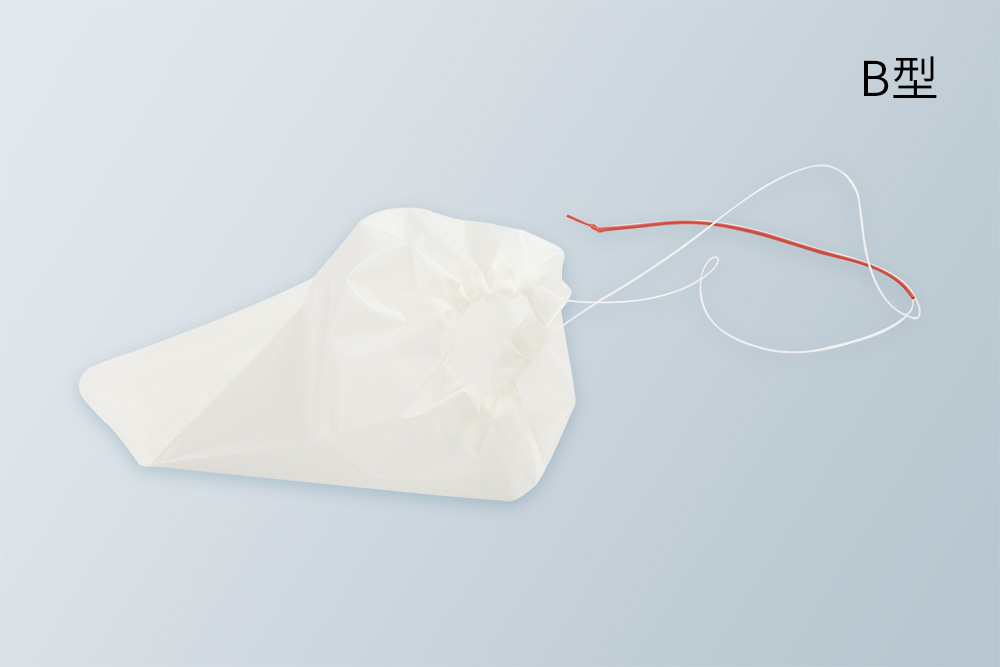

健瑞宝标本取出袋可用于胸或腹腔镜手术中,在胸或腹腔内盛装切除的标本并将此标本取出。产品采用柔软超强材质,抗爆破压高,防止漏液。有两种不同款式,按需选用,灵活方便。产品有多种规格及尺寸,适合于手术切除的不同尺寸标本。

健瑞宝标本取出袋可用于胸或腹腔镜手术中,在胸或腹腔内盛装切除的标本并将此标本取出。产品采用柔软超强材质,抗爆破压高,防止漏液。有两种不同款式,按需选用,灵活方便。产品有多种规格及尺寸,适合于手术切除的不同尺寸标本。

● 超强材料制成标本袋,抗拉抗内爆破压,防止漏液

● 柔软涂层尼龙袋,袋口抗拉强度大

● 不同张口大小和容量,适用不同标本大小

多种规格可选 不同张口大小和容量,适用不同标本大小

柔软涂层尼龙袋 柔软涂层尼龙袋,袋口抗拉强度大

抗爆破压高 袋内抗爆破压高,防止漏液